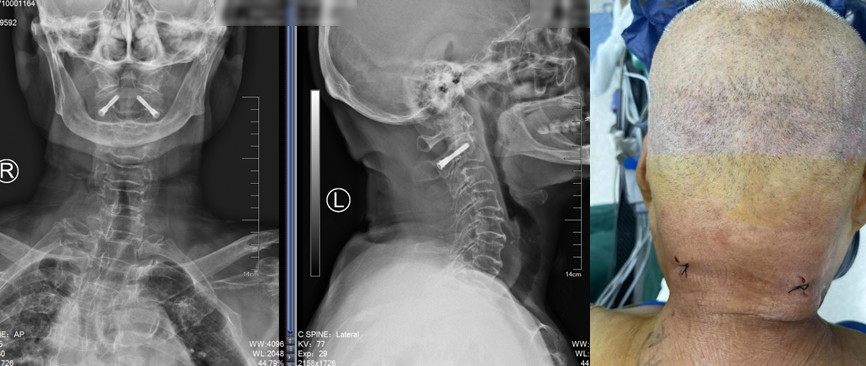

CT重建提示骨折同时合并一侧椎弓根先天性发育性狭窄

入院完善术前检查后,骨科姜为民主任团队在骨科机器人的辅助下,精准而迅速地置入了两枚由团队设计的枢椎椎弓根专用拉力螺钉,仅留下两个不足1cm的切口。手术过程顺利,手术时间仅38分钟。患者术后第一天就可以佩戴颈托下床行走,第二天即可出院回家休养。

术后复查提示骨折复位,置钉精准